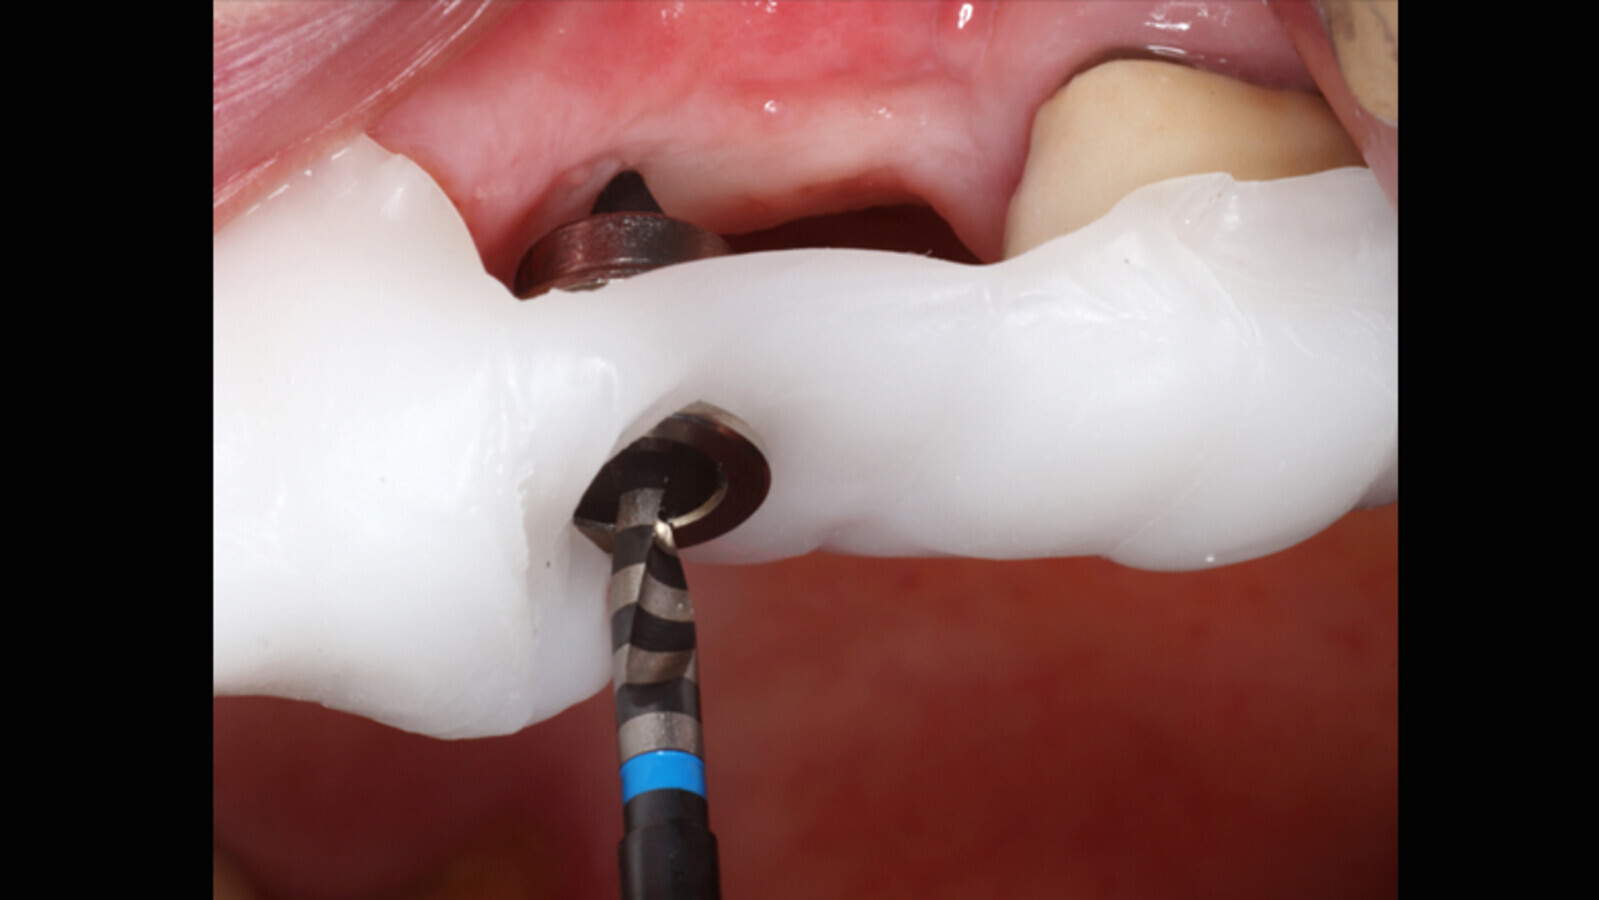

Figura 1. Inicialmente, se debe tener la guía quirúrgica preformada.

Figura 5a. Cirugía con la guía quirúrgica y colocación del implante.

Figura 5b. Cirugía con la guía quirúrgica y colocación del implante.

Figura 5c. Cirugía con la guía quirúrgica y colocación del implante.